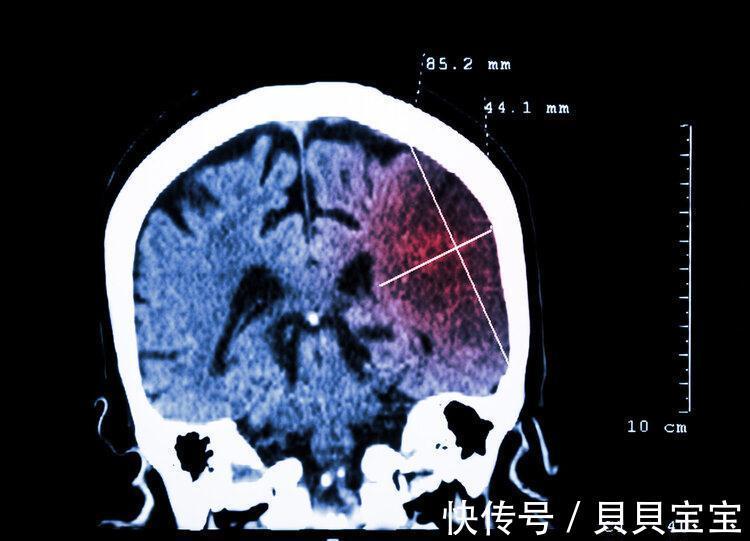

随着生活水平的提高,我们可以发现越来越多的疾病向我们慢慢靠拢。2019年《柳叶刀》的神经病学子刊发布了一则数据:2016年,全球发生脑梗总人数大约为1370万,而我国则高达551万人,占比2/5,死亡人数则高达179万人,占比3/10。

脑梗是指因脑部血液供应障碍,缺血、缺氧所导致,通常发生在中老年人身上的一种疾病,那么它于我们的生活息息相关吗?